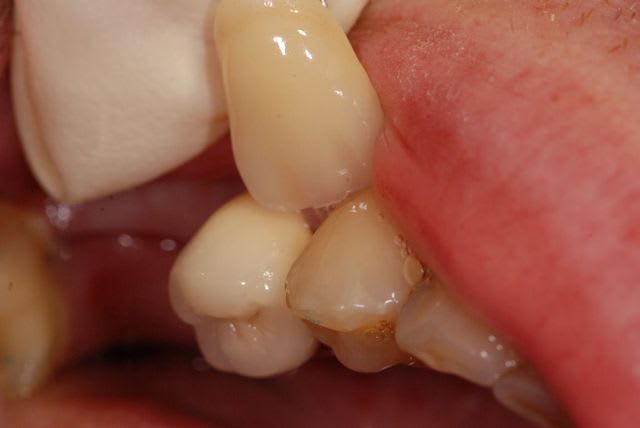

Pour ceux qui émettaient l'hypothèse du manque de place pour le prothésiste, je n'ai pas de photo en occlusion, mais vous pourrez constater qu'au moins en périphérique il avait largement la place. Et je vous demande de bien vouloir me croire pour la place en occlusal.

Ca n'a rien à voir avec le reste, mais c'est pour faire écho au post de Sid sur les onlays sous gingivaux : je trouve que tu es énormément sous gingival.

Perso, je ne fais jamais de limite si profonde, meme en vestibulaire. Etais tu obligé de le faire ou c'est dans tes habitudes de travail ?